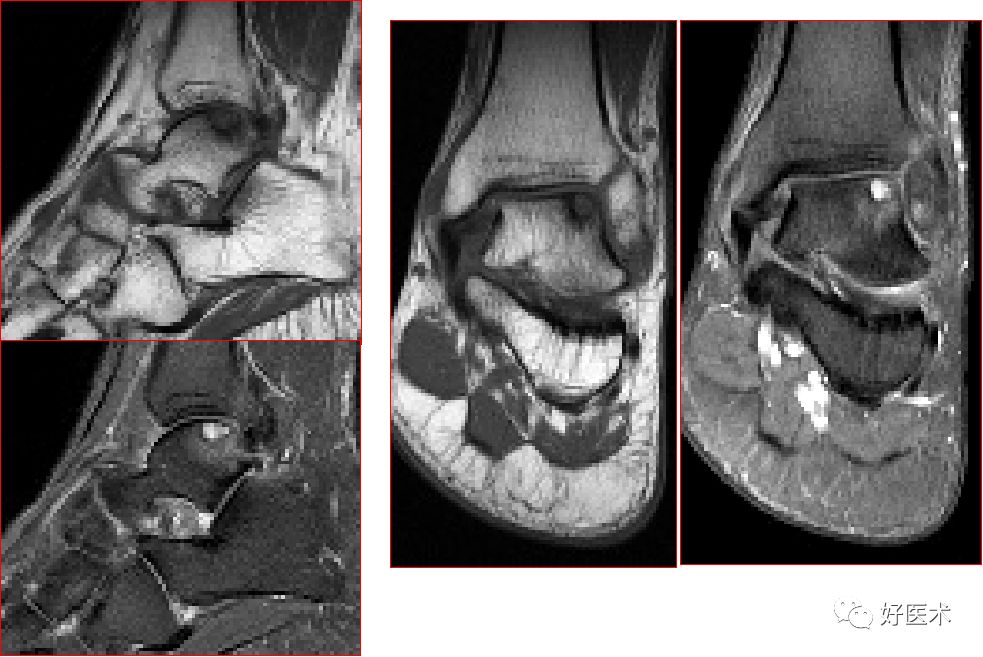

踝关节mri解剖与常见病变,都在这篇文章里!

足底筋膜炎正常足底筋膜足底筋膜炎(注意跟骨内侧结节的局限性水肿)3.